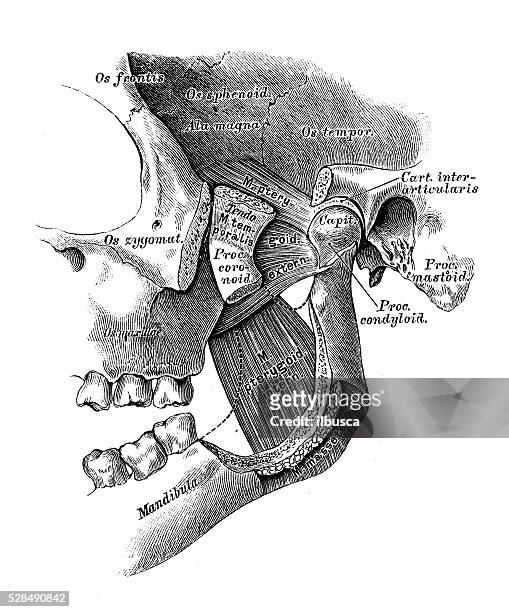

Discover the sophistication of annotated illustration of the jaw's anatomy | stable diffusion online with our curated gallery of numerous images. featuring elegant examples of photography, images, and pictures. ideal for luxury lifestyle publications. Browse our premium annotated illustration of the jaw's anatomy | stable diffusion online gallery featuring professionally curated photographs. Suitable for various applications including web design, social media, personal projects, and digital content creation All annotated illustration of the jaw's anatomy | stable diffusion online images are available in high resolution with professional-grade quality, optimized for both digital and print applications, and include comprehensive metadata for easy organization and usage. Our annotated illustration of the jaw's anatomy | stable diffusion online gallery offers diverse visual resources to bring your ideas to life. Professional licensing options accommodate both commercial and educational usage requirements. Cost-effective licensing makes professional annotated illustration of the jaw's anatomy | stable diffusion online photography accessible to all budgets. Regular updates keep the annotated illustration of the jaw's anatomy | stable diffusion online collection current with contemporary trends and styles. Multiple resolution options ensure optimal performance across different platforms and applications. Time-saving browsing features help users locate ideal annotated illustration of the jaw's anatomy | stable diffusion online images quickly. Whether for commercial projects or personal use, our annotated illustration of the jaw's anatomy | stable diffusion online collection delivers consistent excellence.

![[DIAGRAM] Blank Diagram Of Human Skull - MYDIAGRAM.ONLINE](https://fc05.deviantart.net/fs71/i/2012/270/0/0/annotated_human_skull_anatomy___side_view_by_shevans-d5g1lgl.png)